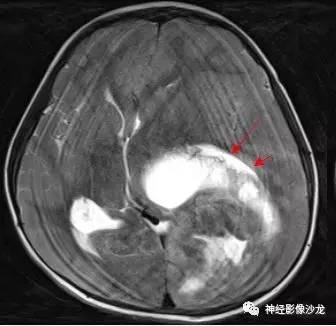

【病例】幕上脑实质内室管膜瘤1例CT及MR影像讨论

箭头标注的地方是左侧脑室后角吧?

这里应该是侧脑室后角

侧脑室三角区受压

儿童,侧脑室三角区旁、囊变、钙化、出血,下次见到首先考虑啊

@神经义工周刚-黄冈市医影像科 pnet还是实性多,幕上室管膜瘤囊性为主,在侧脑室周围。dwi高可能提示间变